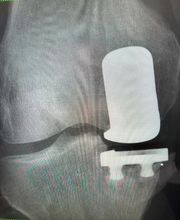

Il Dottor Pera Antonio esercita la professione medica presso il proprio studio ubicato a La Spezia, dove riceve su appuntamento. Pera dr. Antonio è medico chirurgo specializzato in Ortopedia e Traumatologia, anche infantile. Pera dr. Antonio è attualmente iscritto alla S.I.O.T.(Società Italiana di ortopedia e traumatologia); S.I.A.(Società italiana di artroscopia) di cui risulta essere socio onorario; A.L.A.(Associazione ligure di artroscopia); S.I.T.R.A.S.(Società italiana di traumatologia dello sport); S.P.L.L.O.T.(Società piemontese ligure e lombarda di ortopedia e traumatologia); Club di Chirurgia del ginocchio. Dal Gennaio 2012 Pera dr. Antonio svolge il ruolo di Delegato Regionale S.I.A.(Società Italiana di Artroscopia) per la Liguria. Riceve solo su appuntamento.